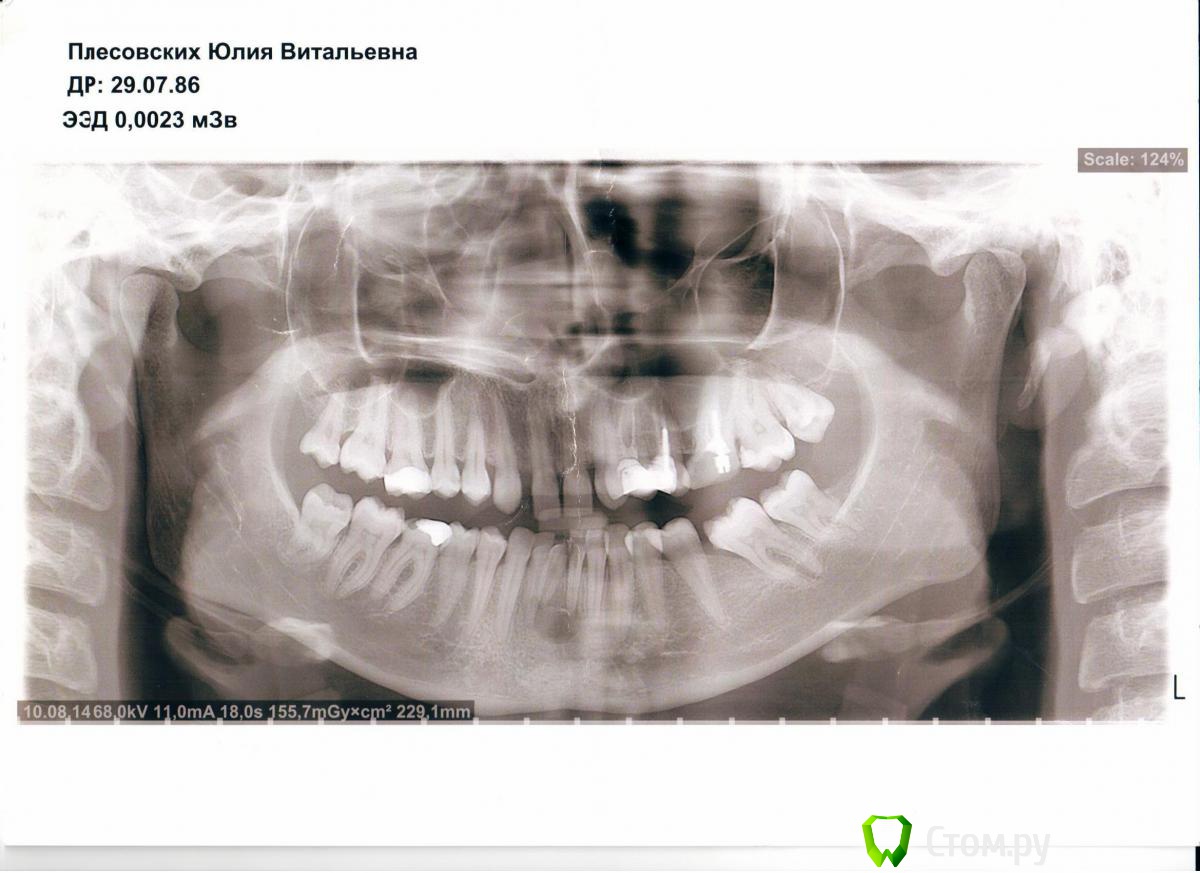

Julia_86 Опубликовано 9 сентября, 2014 Поделиться Опубликовано 9 сентября, 2014 Здравствуйте, прошу совета по дальнейшему лечению. Не знаю верно ли разместила тему, поправьте если что не так.Месяца полтора назад случайно обнаружилась радикулярная киста нижних передних зубов. Хотела поставить брекеты по причине адентии верхних двоек, врач отравил на понорамный снимок - увидели кисту. Зубы, которые охвачены кистой, никогда не болели, но один из зубов изменен в цвете и видимо был травмирован,т.к. видно скол. Терапевт сначала хотела лечить через каналы, закладывая лекарство на полгода, но я засомневалась и пошла к хирургу. Хирург отправила на КТ. В итоге хирург после КТ решила, что центральный резец в кисте нужно удалять(он короче всех) и делать операцию одновременно. Во время операции заложить костнозамещающий материал (bio-oss) и ждать пока все восстановиться.Но есть один момент - чтобы остальные 2 зуба, которые в кисте, не выпали, врач предлагает или поставить брекеты перед операцией, чтобы они не давали зубам шевелиться после операции. Позже, когда все зарастет и костная ткань восстановиться - брекетами восстановить зубной ряд из 3х резцов. Сейчас на нижней челюсти скученность, после удаления как раз хватит места для 3х зубов. Либо до операции клеить какую-то штуку на внутреннюю сторону зубов и после операции через 4 месяца протезировать. Зубы, которые в кисте будут депульпированы и запломбированы. Подскажите, какой вариант более целесообразен. Ссылка на комментарий

dr-krasnov Опубликовано 9 сентября, 2014 Поделиться Опубликовано 9 сентября, 2014 Это не радикулярная киста. Стоит подумать о дисплазии. Что скажут коллеги? 1 1 Ссылка на комментарий

kriokov Опубликовано 9 сентября, 2014 Поделиться Опубликовано 9 сентября, 2014 Что скажут коллеги? думаю, что надо проверить нижние резцы на витальность (живы или нет), если травма в истории и зуб потемневший умер , то скорее киста. По лечению-- фото бы зубов во рту, и данные теста на витальность зубов. 3 Ссылка на комментарий

dr-krasnov Опубликовано 9 сентября, 2014 Поделиться Опубликовано 9 сентября, 2014 Я не уверен, и смайлик соответствующий. Много раз наблюдал аналогичную картину на витальных зубах. Обратите внимание на анамнез. Находка случайна, пациент о ней не подозревал, стало быть травма и клиника отсутствовали. Признаков ранее проведенного лечения - тоже нет. Стало быть - это не радикулярная киста. Вот вкратце ход моих суждений ). Ссылка на комментарий

kriokov Опубликовано 9 сентября, 2014 Поделиться Опубликовано 9 сентября, 2014 стало быть травма и клиника отсутствовали скол на зубе и изменение цвета одного из зубов. Но, согласен мало этого, для диагноза 3 Ссылка на комментарий

Bier Опубликовано 10 сентября, 2014 Поделиться Опубликовано 10 сентября, 2014 Автор, сфотографируйте нижние зубы пожалуйста.Не надо торопиться с хирургией.План действий такой: определить витальные (живые) ли зубы, находящиеся в полости кисты. Скорее всего потемневший зуб мертв. Тогда надо провести терапевтическое лечение, через канал, желательно только терапевта поискать с микроскопом.Если все зубы живые, как предположил коллега, тогда к хирургу с обязательной гистологией образования. 1 Ссылка на комментарий